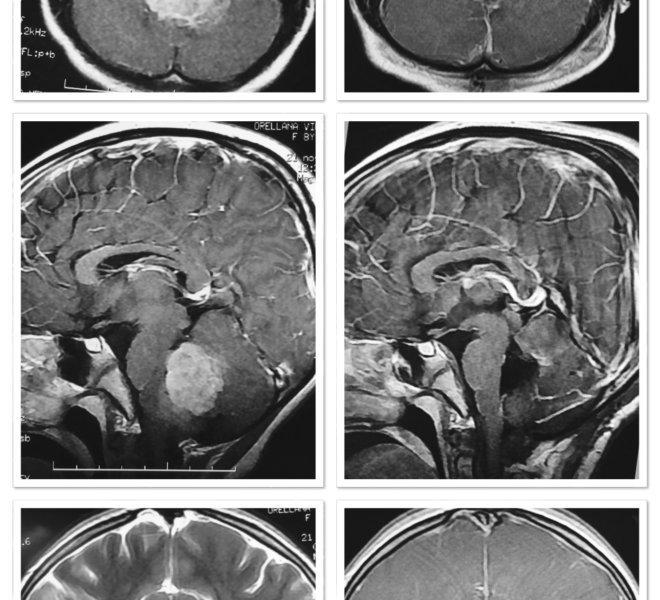

MEDULOBLASTOMA

DESCRIPCIÓN